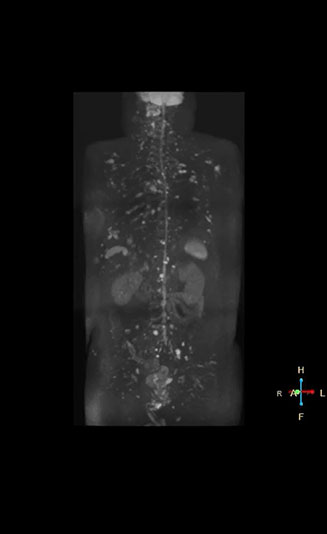

“Switching to coronal DWIBS – rather than axial – further shortens scan time,” says Mr. Naka. “Important is that a dS SENSE factor of 5 shortens exam time while high image quality can be maintained, thanks to Ingenia’s dStream architecture.” He adds that the coronal orientation also avoids artifacts that are specific to combining axial images.

“When we use a coronal DWIBS acquisition, we can perform a full whole body examination, including other required sequences, within 30 minutes,” he says.